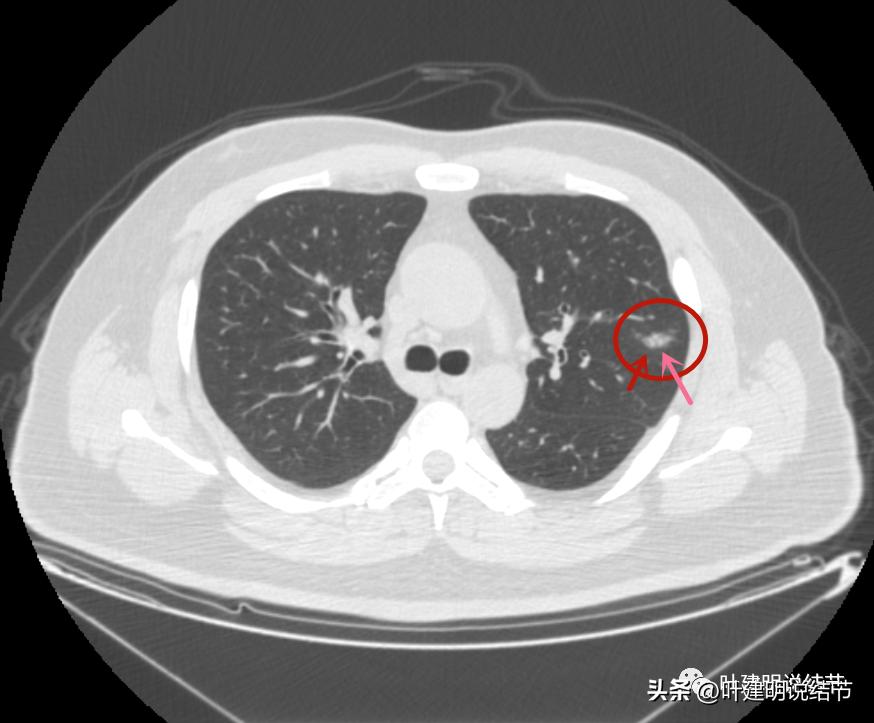

病灶2出现,还只有一点点磨玻璃影,血管走行有点异样

密度略显高,有微血管进入(桔色箭头),边缘略模糊,但轮廓还是较清

中间有实性成分出现(粉色箭头),微血管进入明显(桔色箭头),边上有磨玻璃成分(绿色箭头),整体轮廓清

病灶密度不均

密度不均显杂乱

表面略不平

整体瘤肺边界与轮廓较清

边上另有病灶出现,即左上病灶3(蓝色箭头)

病灶3也有微血管进入(桔色箭头)

病灶3密度不均,轮廓清,有细毛刺样征(紫色箭头)

瘤现边界清

边上似乎有斑点状(绿色箭头),是不是卫星灶?

似乎有偏实性成分出现,密度较为杂乱

密度不均,瘤肺边界清,似乎是乱石征的影像

有偏实性成分,表面不平,边缘似乎有磨玻璃密度的成分

毛刺征(紫色箭头),微血管征(桔色箭头),实性点状成分(粉色箭头),整体轮廓较清(红色箭头)

血管弯征(桔色箭头)

血管进入

病灶3边缘部分的样子